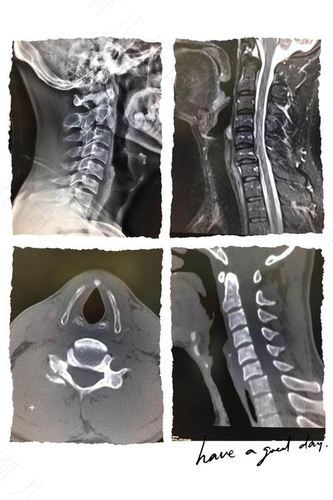

3. X光片主要应用于检查一些外伤骨质损伤,能够较为快速准确得到结果。而对于一些腰椎病和颈椎病,以及相应的神经根等组织疾病就需要选择核磁共振的检查方式,特别是对一些脂肪组织,肌肉组织的检查,通过核磁共振能够较好的对此部位疾病做出较为准确的诊断。